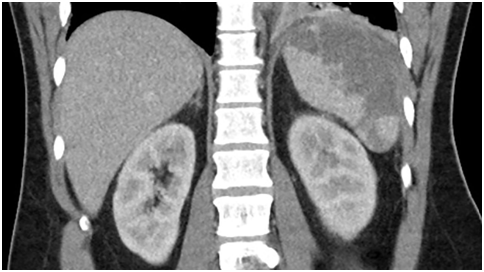

A 31-year-old Caucasian man presented to the hospital with 4day-history of left upper quadrant abdominal pain and left sided pleurisy. He had recently failed therapy for chronic HCV mono-infection, genotype 1a, with fibrosis score of F0. He admits to using intravenous recreational drugs. Vital signs were normal except for heart rate of 130/min. The abdomen was tender in the left upper abdominal quadrant with no of peritoneal irritation. Initial blood investigations revealed leukocytosis of 21.3x103/µl with normal renal function and liver enzymes. Computed tomography of the abdomen with IV contrast showed a large splenic infarct (Figure 1). He had no recent abdominal trauma or abdominal surgery. Streptococcus constellatus was cultivated from two sets of blood cultures on day three. Comprehensive workup excluded mononucleosis, pancreatic disorders, HIV, autoimmune/collagen vascular disease, sickle hemoglobinopathies, malignant hematologic disorders (normal peripheral blood smear, SPEP and flow cytometry), hepercoagulable state (normal protein C or protein S; normal lupus anticoagulant, factor V, prothrombin). Patient had no signs of ARDS, sepsis, septic shock or toxic shock syndrome. Patient no recent cardiac catheterization (angiographic embolization), sclerotherapy of esophageal varices, abdominal surgery (pancreatectomy, or liver transplant), vasopressin infusion, or embolization for splenic hemorrhage. Echocardiogram showed the presence of 2.5x1.5cm2 vegetation of the aortic valve with perforation, severe regurgitation and aortic root abscess (Figure 2). Magnetic resonance imaging (MRI) of the brain showed numerous brain abscesses, without mass effect or midline shift. This case was complex and Duke’s criteria were used to make the diagnosis of IE. The patient received aortic valve replacement and his post-operative course was uneventful. Administration of ertapenem was continued for 8 weeks. The patient had full neurological recovery and repeat MRI of the brain showed complete resolution of the abscesses. Follow-up echocardiogram showed no thrombosis or vegetation of the bioprosthetic valve.

Figure 2A) Echocardiogram showed the presence of 2.5x1.5cm2 vegetation of the aortic valve.